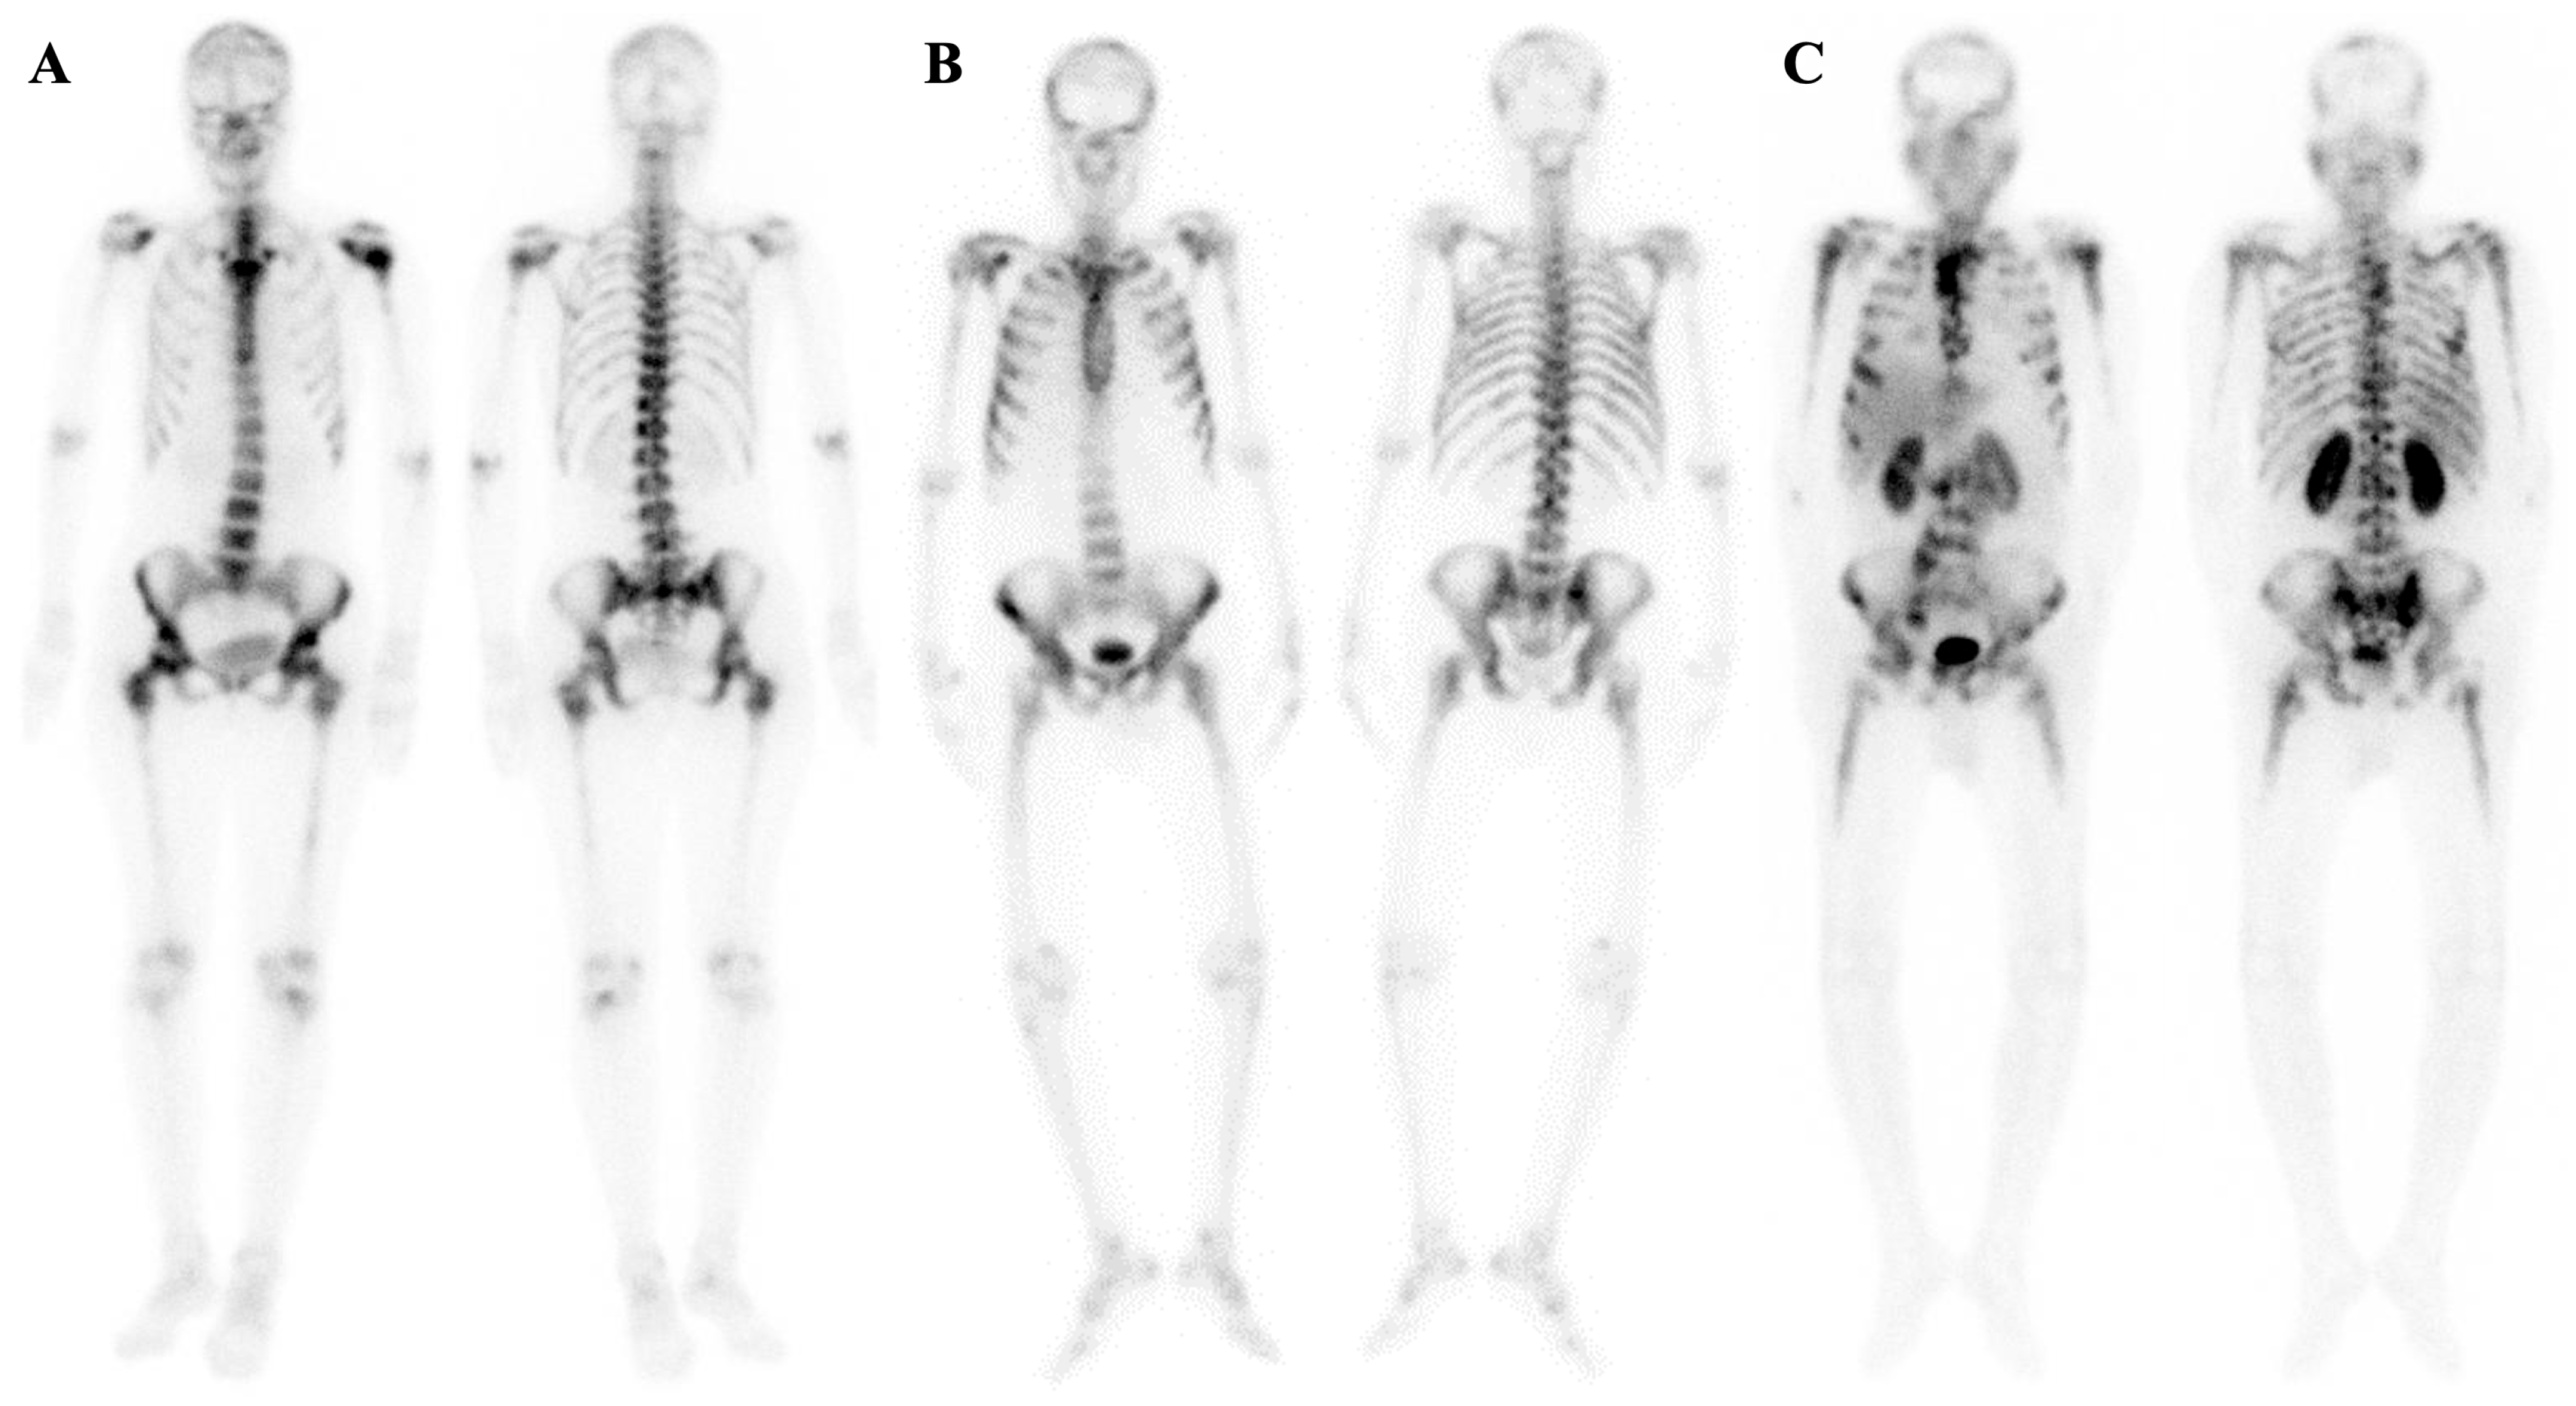

7.1.2. Dynamic Changes in Prostate Cancer Patients with Superscan